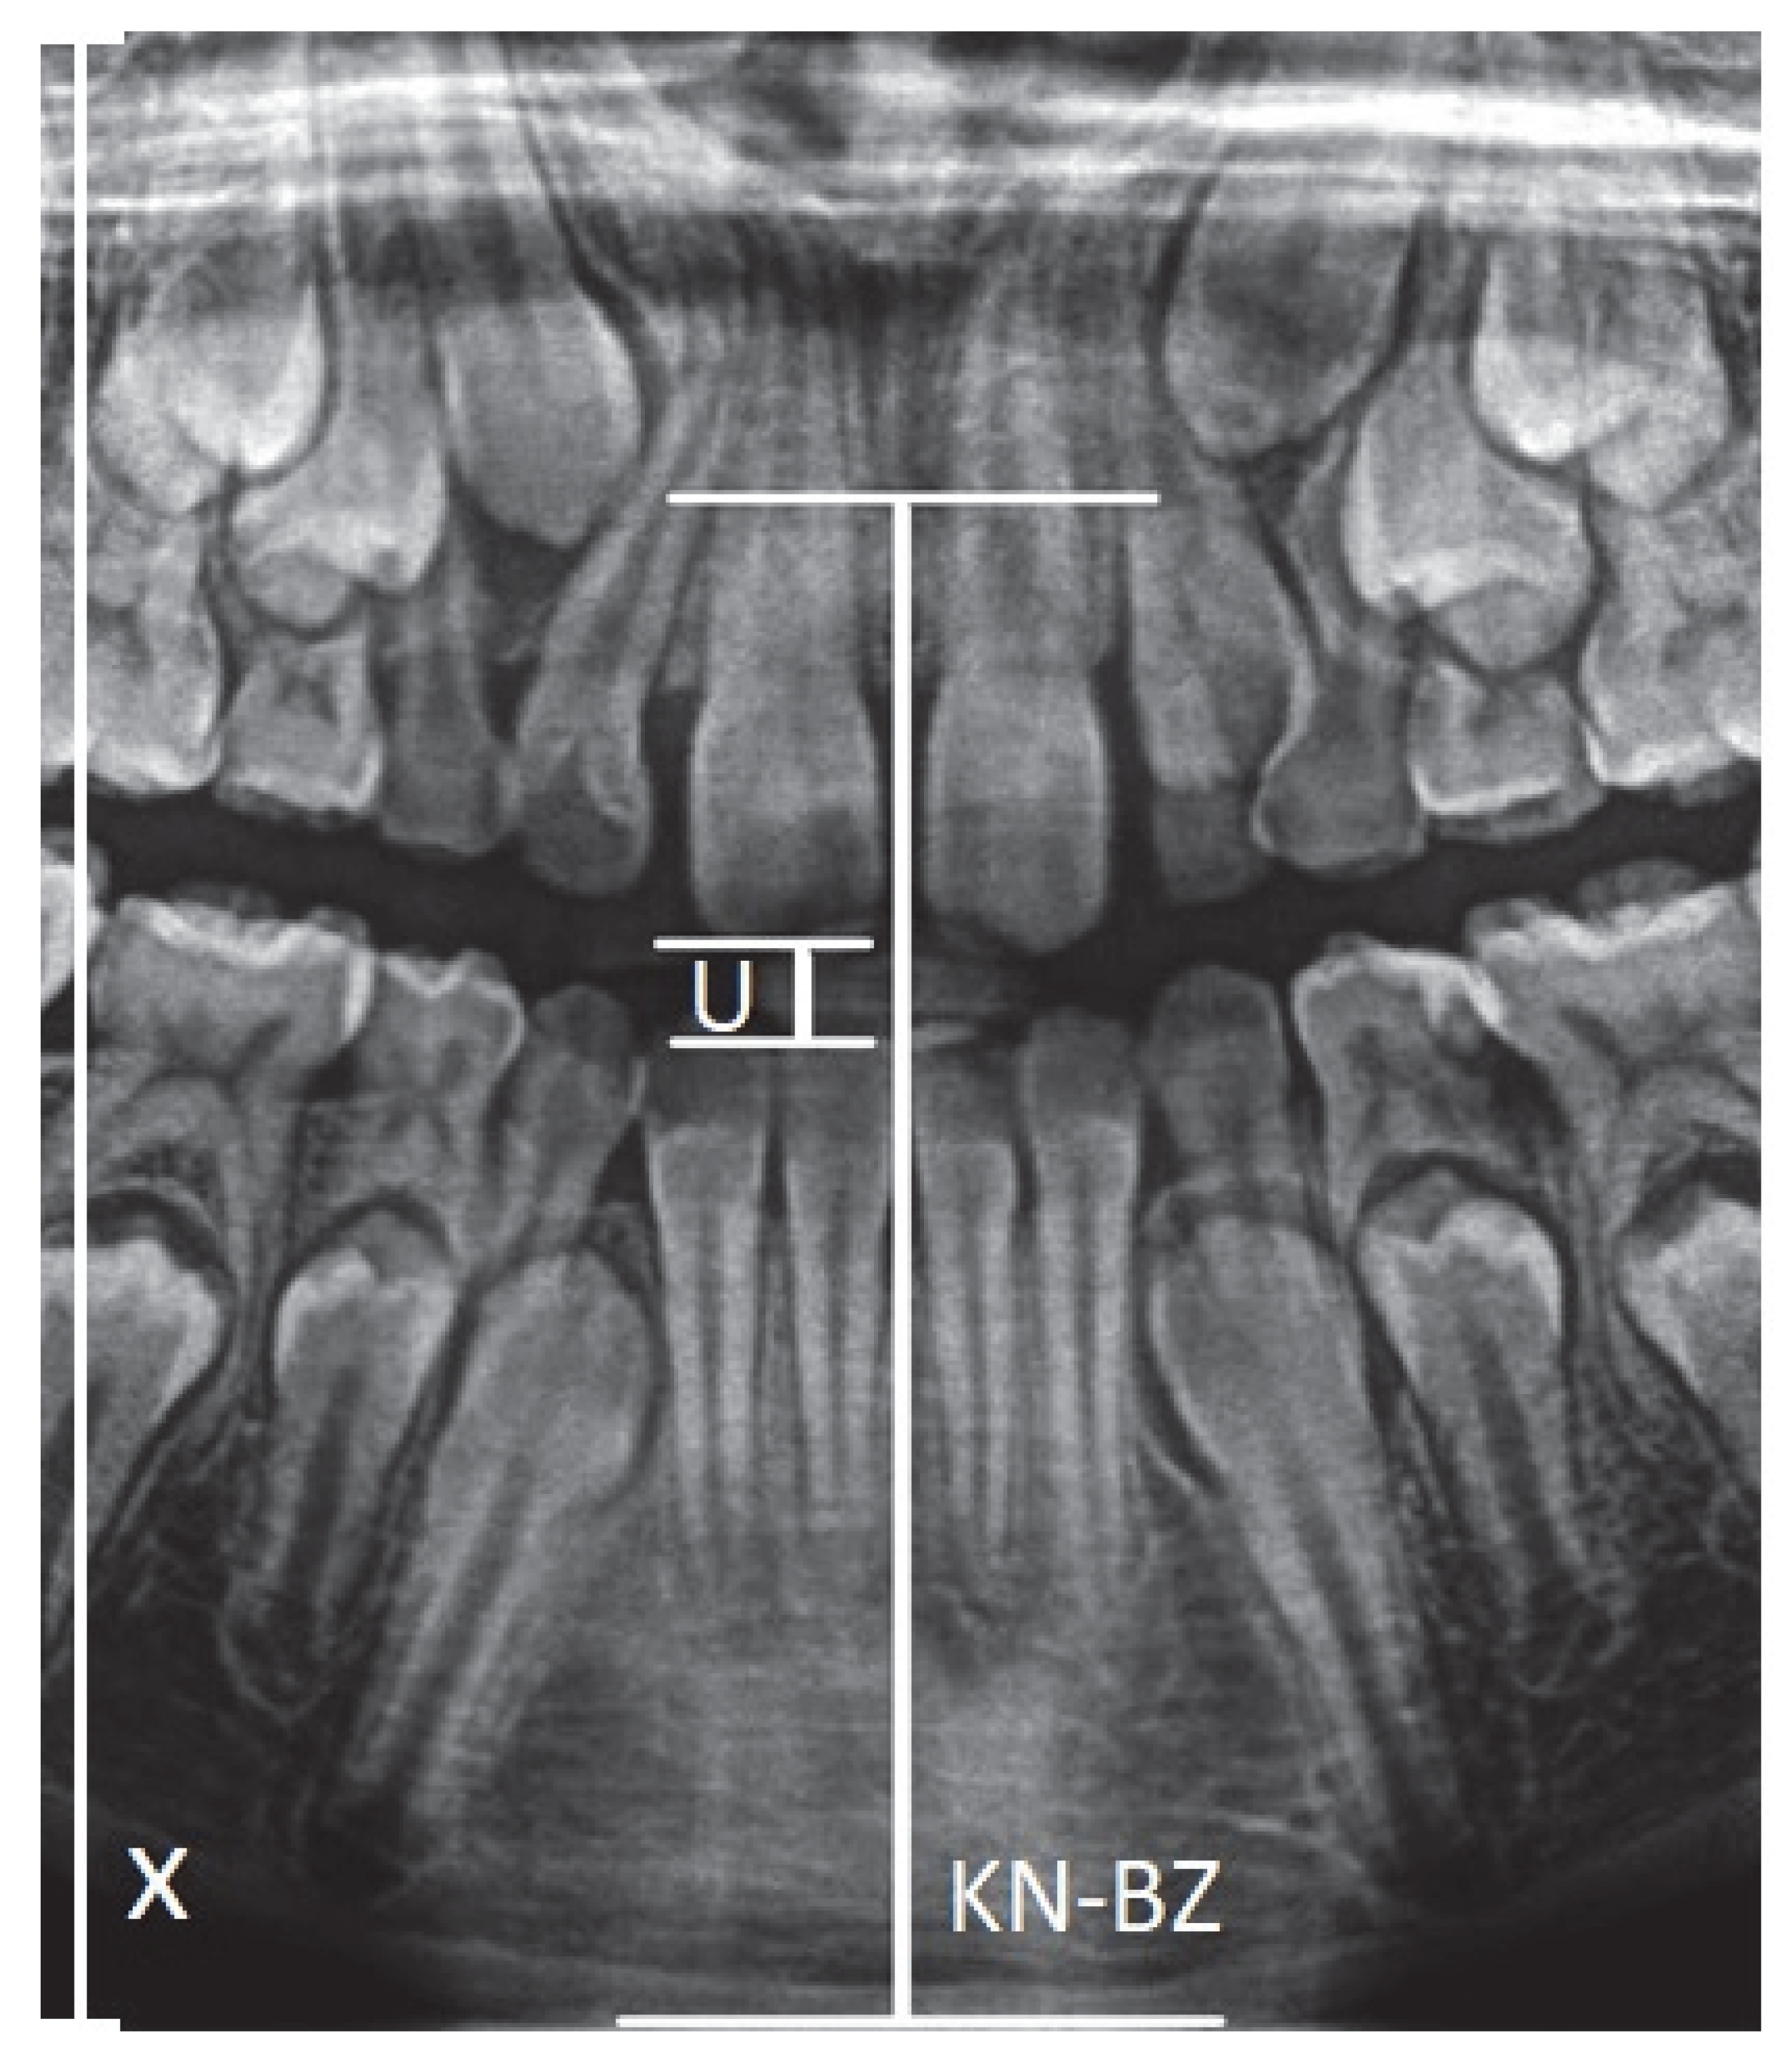

- X-axis—Left vertical edge of the pantomographic radiograph.

- U—Width of the mouthpiece of the X-ray equipment.

- KN-BZ—Distance of the anterior nasal spike from the mandibular margin.